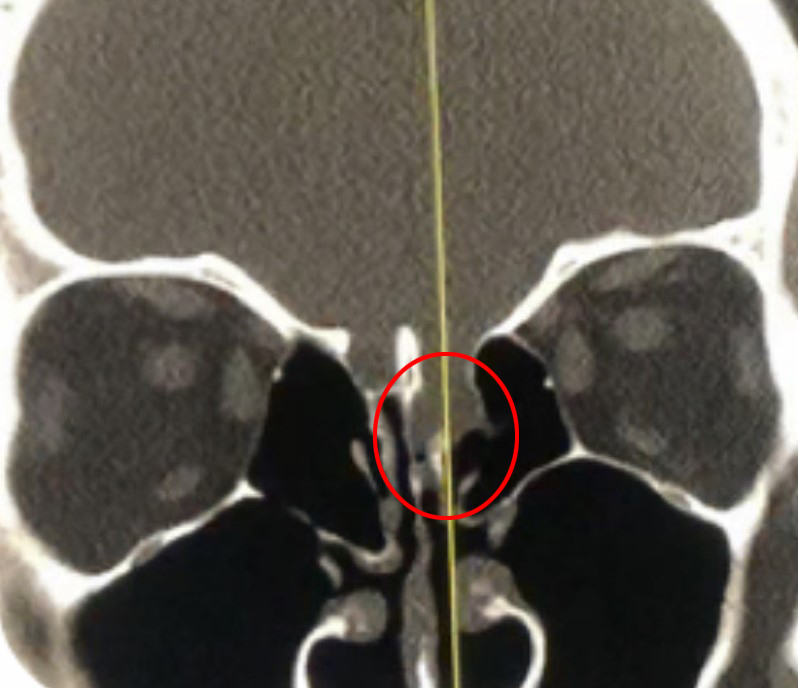

This is a 39 year old physician with a long history of sinus issues, who more recently had noted an increased drainage of clear fluid from his nose. Testing of the fluid for Beta-2-transferrin demonstrated that it was consistent with cerebrospinal fluid (csf). MRI and CT scan demonstrated an encephalocele in the frontal most part of the anterior skull base, on the left, just off midline (Figures 1a,1b,1c). For the last 3 weeks, he has also been having headaches and neck pain.

Figure 1a – Coronal CT bone window

Figure 1b – Sagittal CT bone window